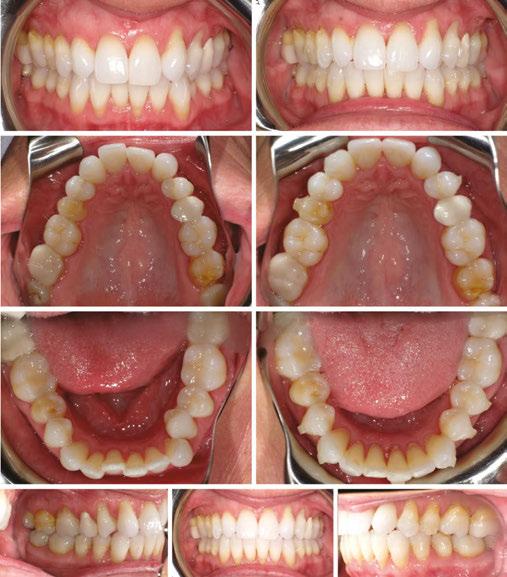

Figures 1-5: Initial dental photos

analysis showed that she had a brachycephalic skeletal pattern, but ANB and inter-incisal angles were normal. Occlusal wear in and of itself does not affect patient quality of life,3 but some patients are self-conscious about the appearance of their short, worn teeth, which is the category that this patient fits into. Her chief concern was to improve her dental esthetics.

Figures 11 and 12: Final frontal and occlusal with spacing

Figures 13-17: Final restorative photos